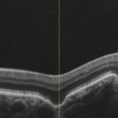

Focal Choroidal Excavation Focal Choroidal ExcavationJan 6 2019 by Aristofanes Canamary jr A 51-year-old female who reported low visual acuity on AO, worse in the OE. Fundoscopy of OE is observed color and brightness alteration in macular region. Focal concave-shaped chorioretinal anomaly in the foveal region and other two anomaly peripapilary and temporal to the fovea with a hyporreflective subretinal space distinguishing from each other. Photographer: Aristófanes Canamary Jr, UPO ophthalmology, Sao Paulo Condition/keywords: excavation, optical coherence tomography (OCT), pachychoroid